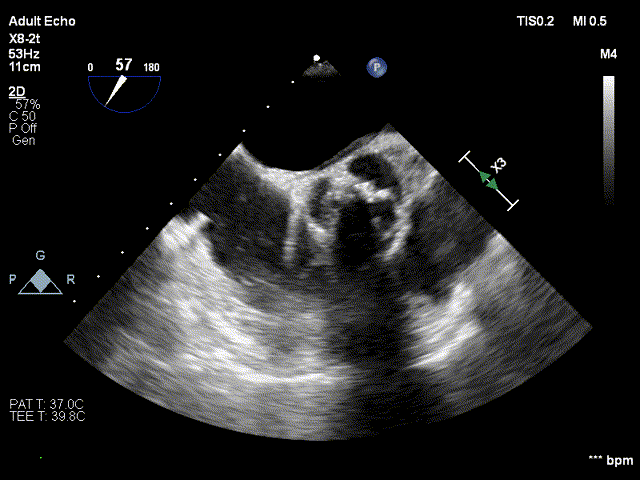

术前超声

术前超声-短轴切面

术前超声-长轴切面